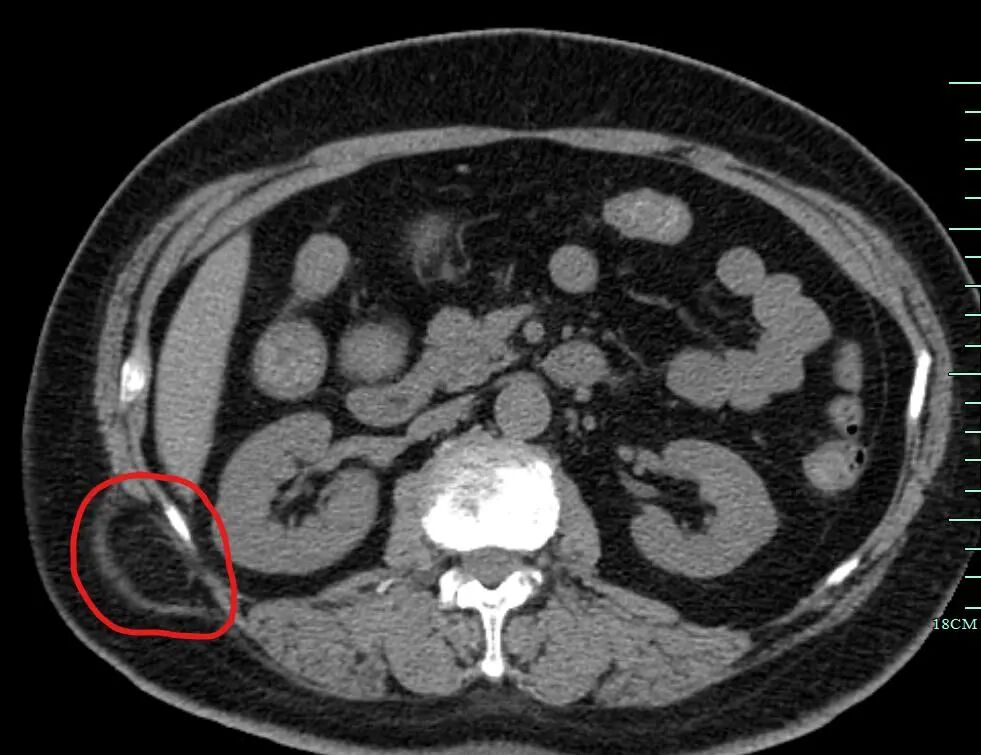

今年65歲的張阿姨,無意中發(fā)現(xiàn)右腰部有一約雞蛋大小的腫塊,平躺時會變小,起初并沒有當回事,后來活動和久站之后,腫塊明顯變大且腰部疼痛,來到我院普通外科就診。

結合病史、查體、彩超及腹部CT檢查結果,臨床診斷為:右側腰疝。